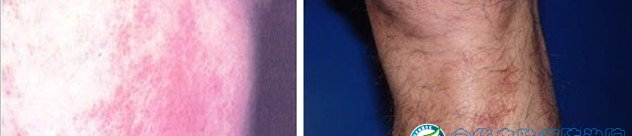

皮炎是一種常見皮膚病,表現(xiàn)為紅斑,表面有針尖至米粒大小的丘疹、水皰、滲透液、結(jié)痂及脫屑,也可呈現(xiàn)苔蘚樣變,自覺瘙癢,日曬和遇熱后會使癥狀加重等現(xiàn)象。醫(yī)生建議,對于已經(jīng)出現(xiàn)皮炎或者過敏癥的人,應(yīng)到正規(guī)醫(yī)院診治。下面是皮炎的圖譜,如果你懷疑自己得了皮炎,可以對照下面譜圖;

三、接觸性皮炎